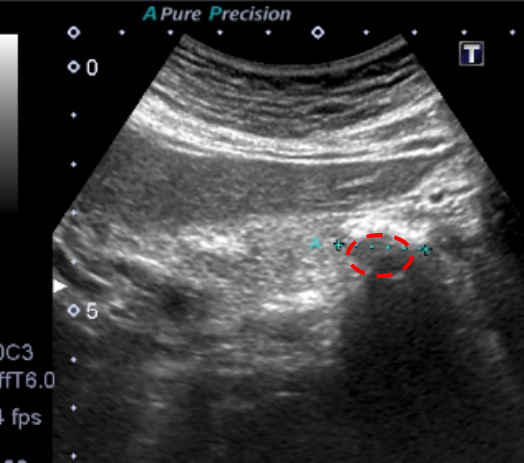

■実際のエコー画像①■

矢印に挟まれた黒い部分が膵管です。通常の3倍以上に拡張している状態でした。